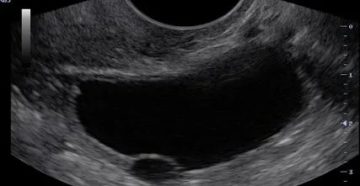

Как делают УЗИ на определение кисты яичника и как разные виды выглядят на мониторе ›…